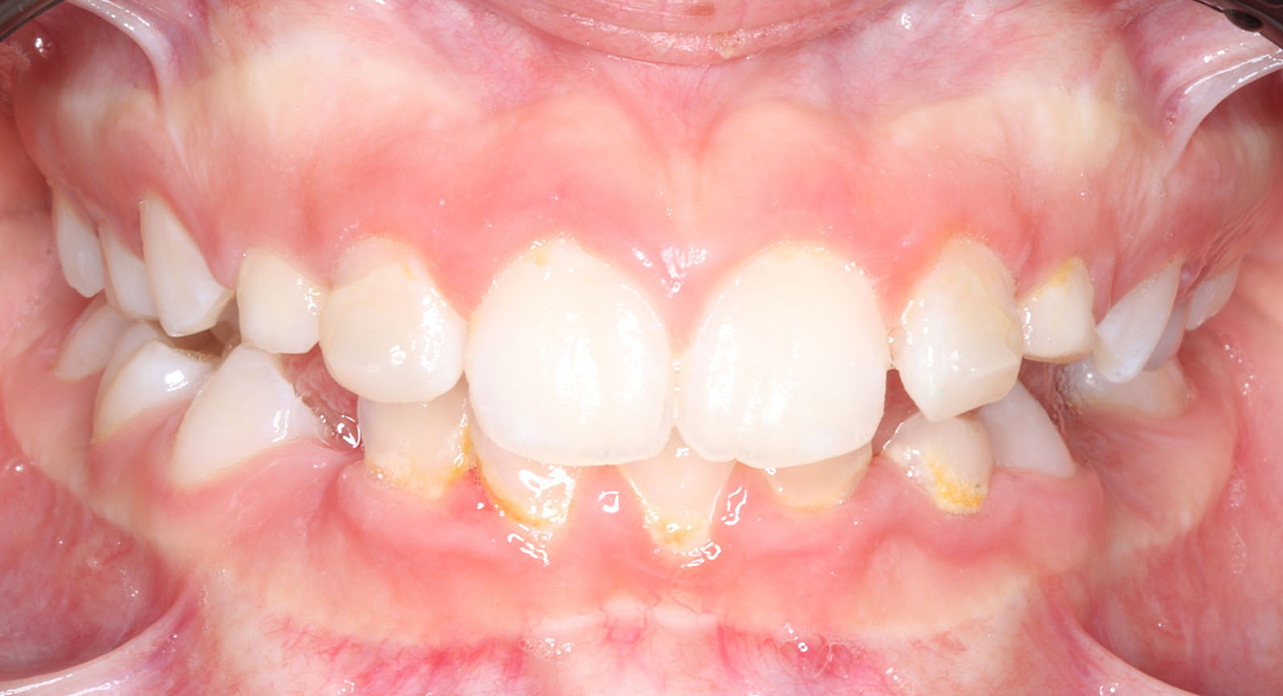

Case report of a 9-year-old female patient in the intermediate phase of mixed dentition. The patient presents with moderate upper and lower crowding, narrow arches, Class II molar relationship on the right side, premature loss of tooth 83, deviation of the lower midline to the right, deep bite, and a crossbite on the right side affecting only the deciduous dentition.

The first aligner set was designed for the development of the upper arch and to create overjet. No aligners were planned for the lower arch to ensure overjet and to facilitate the adaptation process for a 9-year-old patient. If planned today, I would have requested both upper and lower aligners.

After 3 months of using upper aligners, a refinement was requested to begin treatment with aligners on both arches.